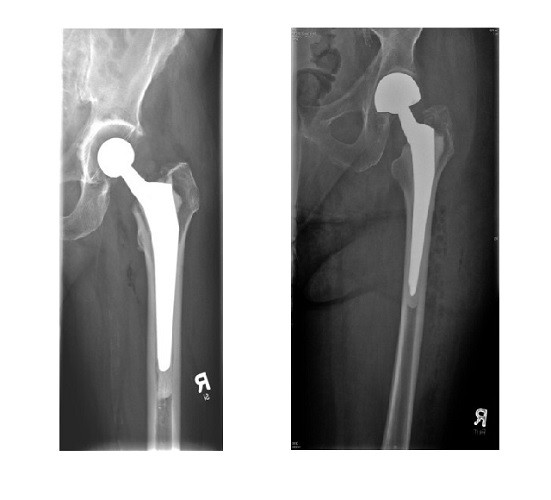

Die beste Behandlung der noch agilen Patienten ist eine Totalendoprothese mit einem zementierten Langschaft (Bild links). Die gebrechlicheren Patienten profitieren von einer kürzeren Operation und weniger Luxationen durch Duokopfprothesen mit zementiertem Langschaft. Nach Luxationen und bei Gelenkdysplasien werden duo-mobile, tripolare Prothesen mehr und mehr eingesetzt.